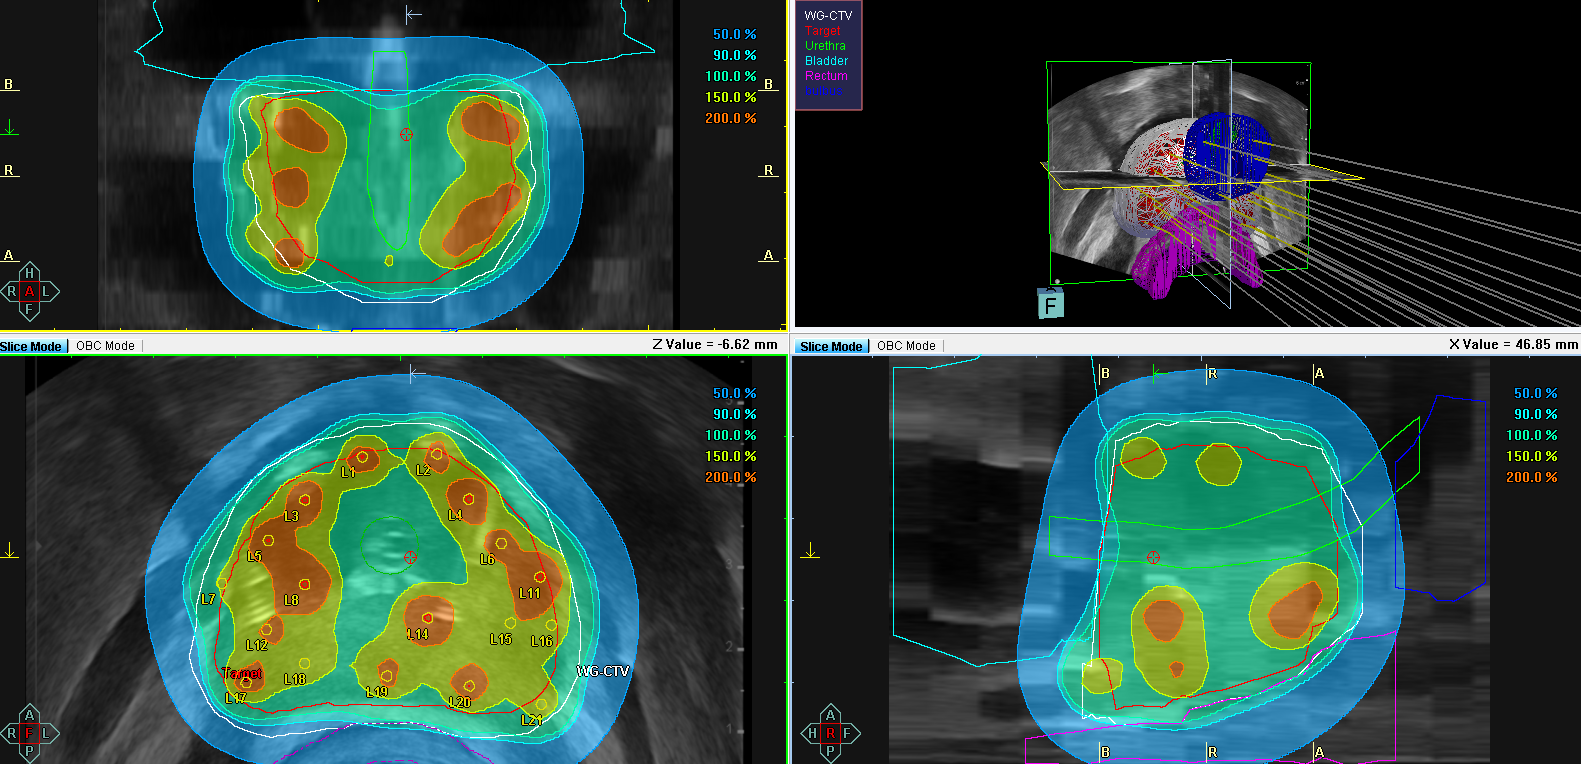

Na terenie Zakładu Brachyterapii WCO prowadzimy badanie kliniczne POWER (z ang. Partial Or Whole gland for ERections) dla osób aktywnych seksualnie z rakiem prostaty w grupie niskiego i pośredniego ryzyka. Jest to międzynarodowe badanie wieloośrodkowe prowadzone przez Uniwersytet w Amsterdamie, a głównym badaczem jest były prezydent GEC-ESTRO Bradley Peters. Badanie ma na celu ocenę zachowania potencji i możliwości współżycia seksualnego u chorych z rakiem prostaty podanych brachyterapii. W trakcie randomizacji pacjenci będą kwalifikowani do leczenia całego gruczołu (grupa kontrolna, Rys. 1) lub leczenia połowy gruczołu krokowego (grupa badana, Rys. 2).